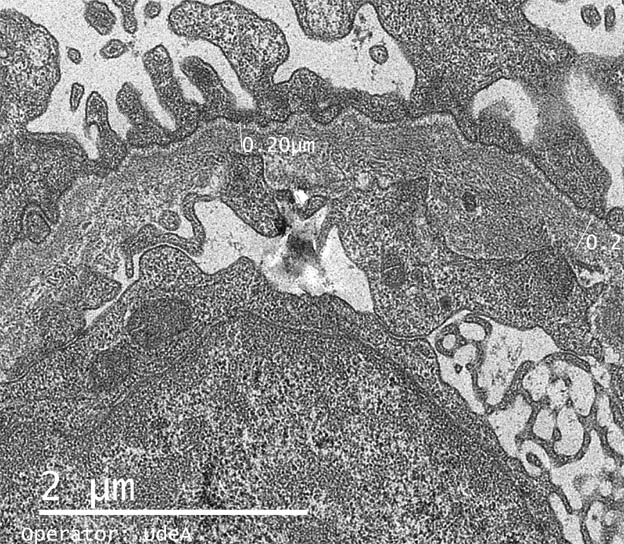

Figure 9. Electron microscopy, X4,000.

Figure 10. Electron microscopy, X6,000.